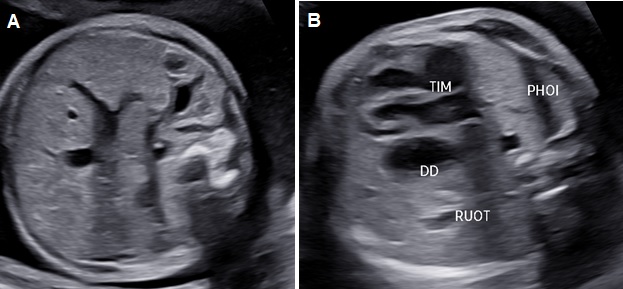

Thoát vị hoành trái: Ở mặt cắt ngang 4 buồng tim có khối phản âm không đồng nhất ở trong lồng ngực trái có thể là dạ dày chứa dịch bên trong (+/-) ruột, gan. Trung thất và tim bị đẩy lệch qua bên phải (Dextroposition). Ở mặt cắt ngang bụng không thấy dạ dày nếu đã bị thoát vị lên lồng ngực.

Thoát vị hoành phải nếu chỉ đơn thuần gan lên có thể khó nhận diện vì phản âm của gan tương tự phổi trên siêu siêu âm thang xám. Hình ảnh đường mật, túi mật là đặc trưng giúp nhận diện gan. Doppler màu có gía trị vì giúp nhận diện các tĩnh mạch gan. Dấu hiệu gián tiếp có thể thấy là hình ảnh trục tim bị lệch.

Đa ối là do thực quản bị chèn ép nên thai khó nuốt và trong hầu hết các trường hợp, đa ối thường xuất hiện sau 26 tuần. Có thể có biến chứng phù thai do trung thất bị di lệch và các mạch máu lớn bi chèn ép, đây là dấu hiệu của tiên lượng nặng.

Hình 2. Thoát vị hoành trái. A: Mặt cắt ngang bụng không thấy dạ dày. B: Mặt cắt ngang 4 buồng tim có hình ảnh dạ dày (DD) và ruột đẩy sát tim qua sát thành ngực phải; phổi phải bị chèn ép.

Hình 3. Thoát vị hoành trái có kèm thiểu sản tâm thất trái